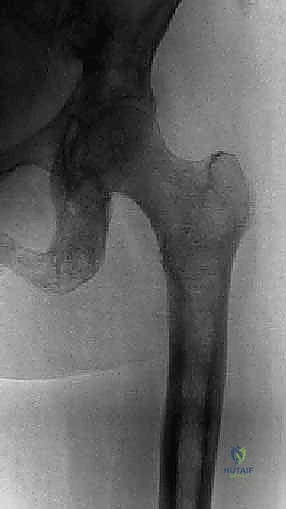

يعتبر مفصل الورك، وخاصة الثلث العلوي من عظم الفخذ (Proximal Femur) ومنطقة الحُق (Acetabulum) في الحوض، من أكثر العظام تعرضاً لهذه النقائل، حيث يمثل منطقة الورك وحدها حوالي 25% إلى 30% من جميع النقائل العظمية في الهيكل العظمي البشري.

2. عظم الفخذ الداني (Proximal Femur): الكرة والرافعة

الجزء العلوي من عظم الفخذ يتكون من:

* رأس الفخذ (Femoral Head): الكرة التي تدخل في الحُق.

* عنق الفخذ (Femoral Neck): يربط الرأس بجسم العظم. وهو من أكثر الأماكن عرضة للكسور المرضية بسبب النقائل.

* المدور الكبير والمدور الصغير (Greater & Lesser Trochanters): نقاط اتصال عضلات الحوض والفخذ القوية. تدمير هذه المناطق بالسرطان يؤدي إلى عرج شديد وعدم استقرار.

- الأشعة السينية العادية (X-rays): الخطوة الأولى والأساسية. تظهر تدمير العظم (الآفات الحالّة) أو زيادة الكثافة غير الطبيعية (الآفات التكوينية).